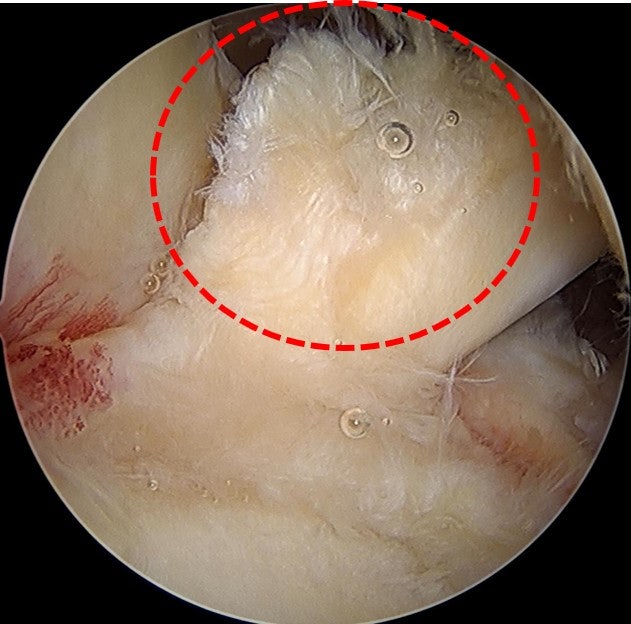

수술을 원래 계획했던 대로 allomend 를 이용하여 회전근개 봉합술 및 봉합술을 시행하였습니다. 수술 직후 MRI 영상으로 확인해 보았습니다.